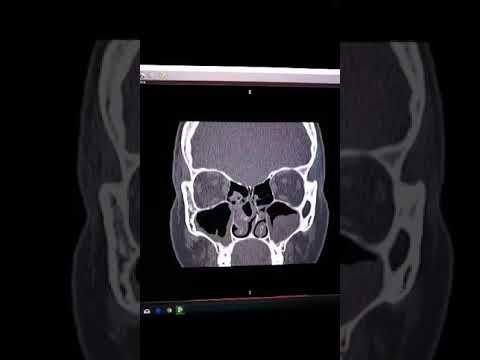

Endoskopowa operacja zatok ( metoda-FESS) wykonywana w WMC.